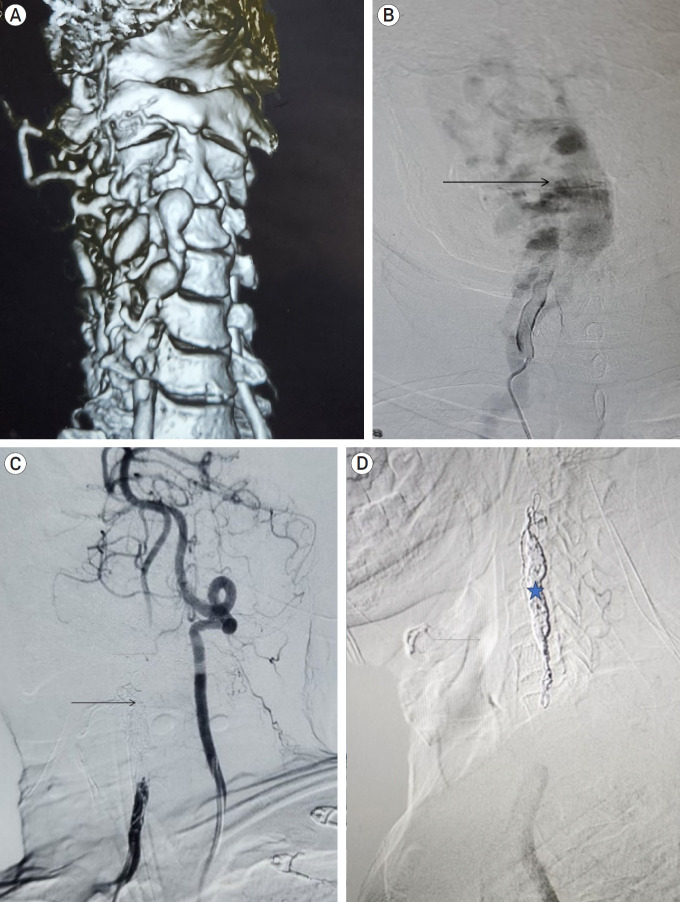

Vertebral-venous fistula (VVF) is a rare vascular disorder characterized by an atypical, direct, high-flow shunt between an extracranial vertebral artery and its adjoining vein. While it can originate spontaneously in association with conditions affecting the vascular wall, trauma is also a recognized etiological factor. We report a case of a 64-year-old gentleman with multiple neurofibromas who presented with a cervical VVF leading to cervical myelopathy, successfully managed with endovascular coiling. The condition's rarity and the complex vascular anatomy involved have hindered the development of standardized management guidelines. Our experience aligns with literature indicating that endovascular treatment can be a safe and effective approach for VVF.